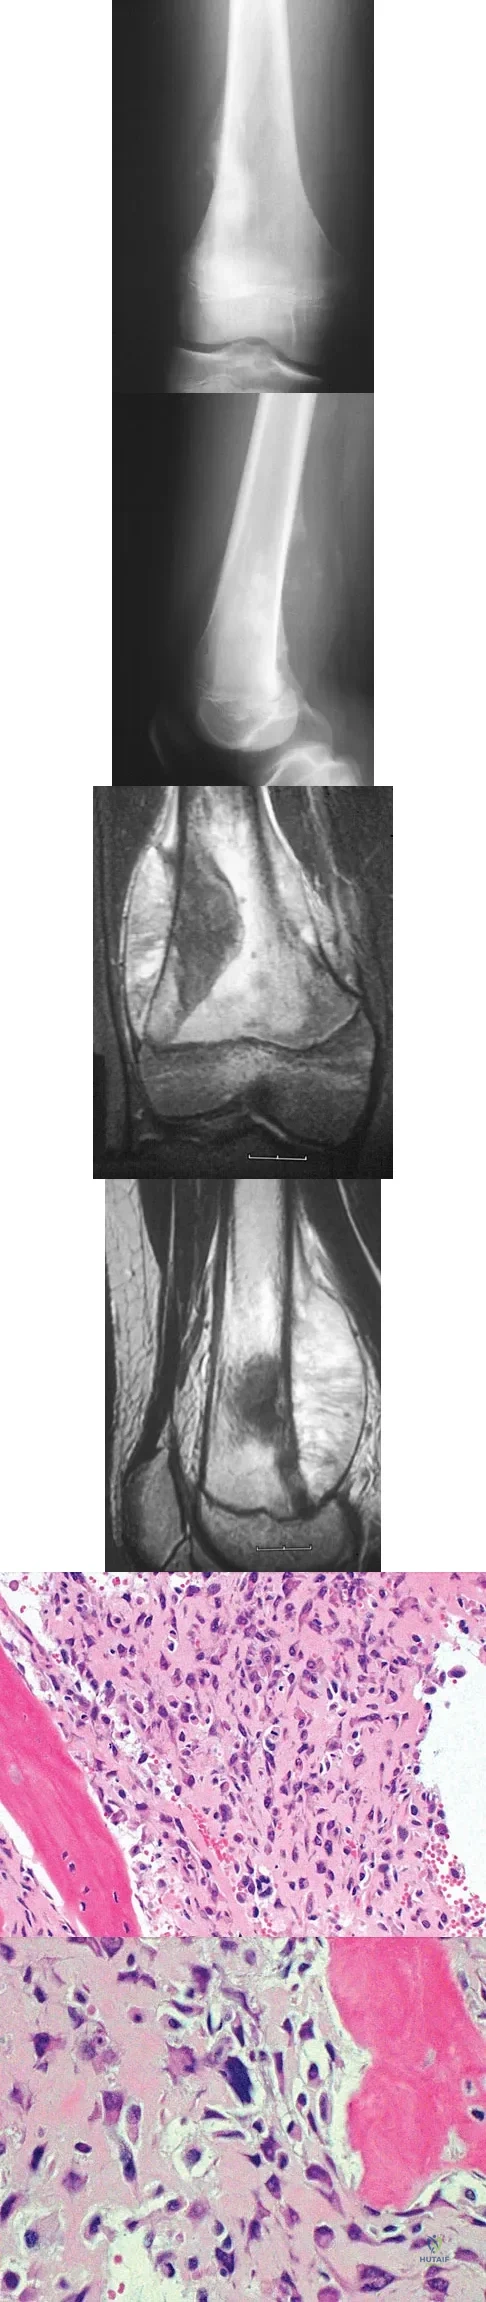

A 13-year-old boy has knee pain after sustaining a mild twisting injury while playing basketball 4 weeks ago. Radiographs and MRI scans are shown in Figures 24a through 24d, and biopsy specimens are shown in Figures 24e and 24f. Treatment should consist of

A 64-year-old man has had increasing pain in the left hip for the past 6 months. A radiograph and MRI scan are shown in Figures 25a and 25b. Biopsy specimens are shown in Figures 25c and 25d. What is the recommended treatment?